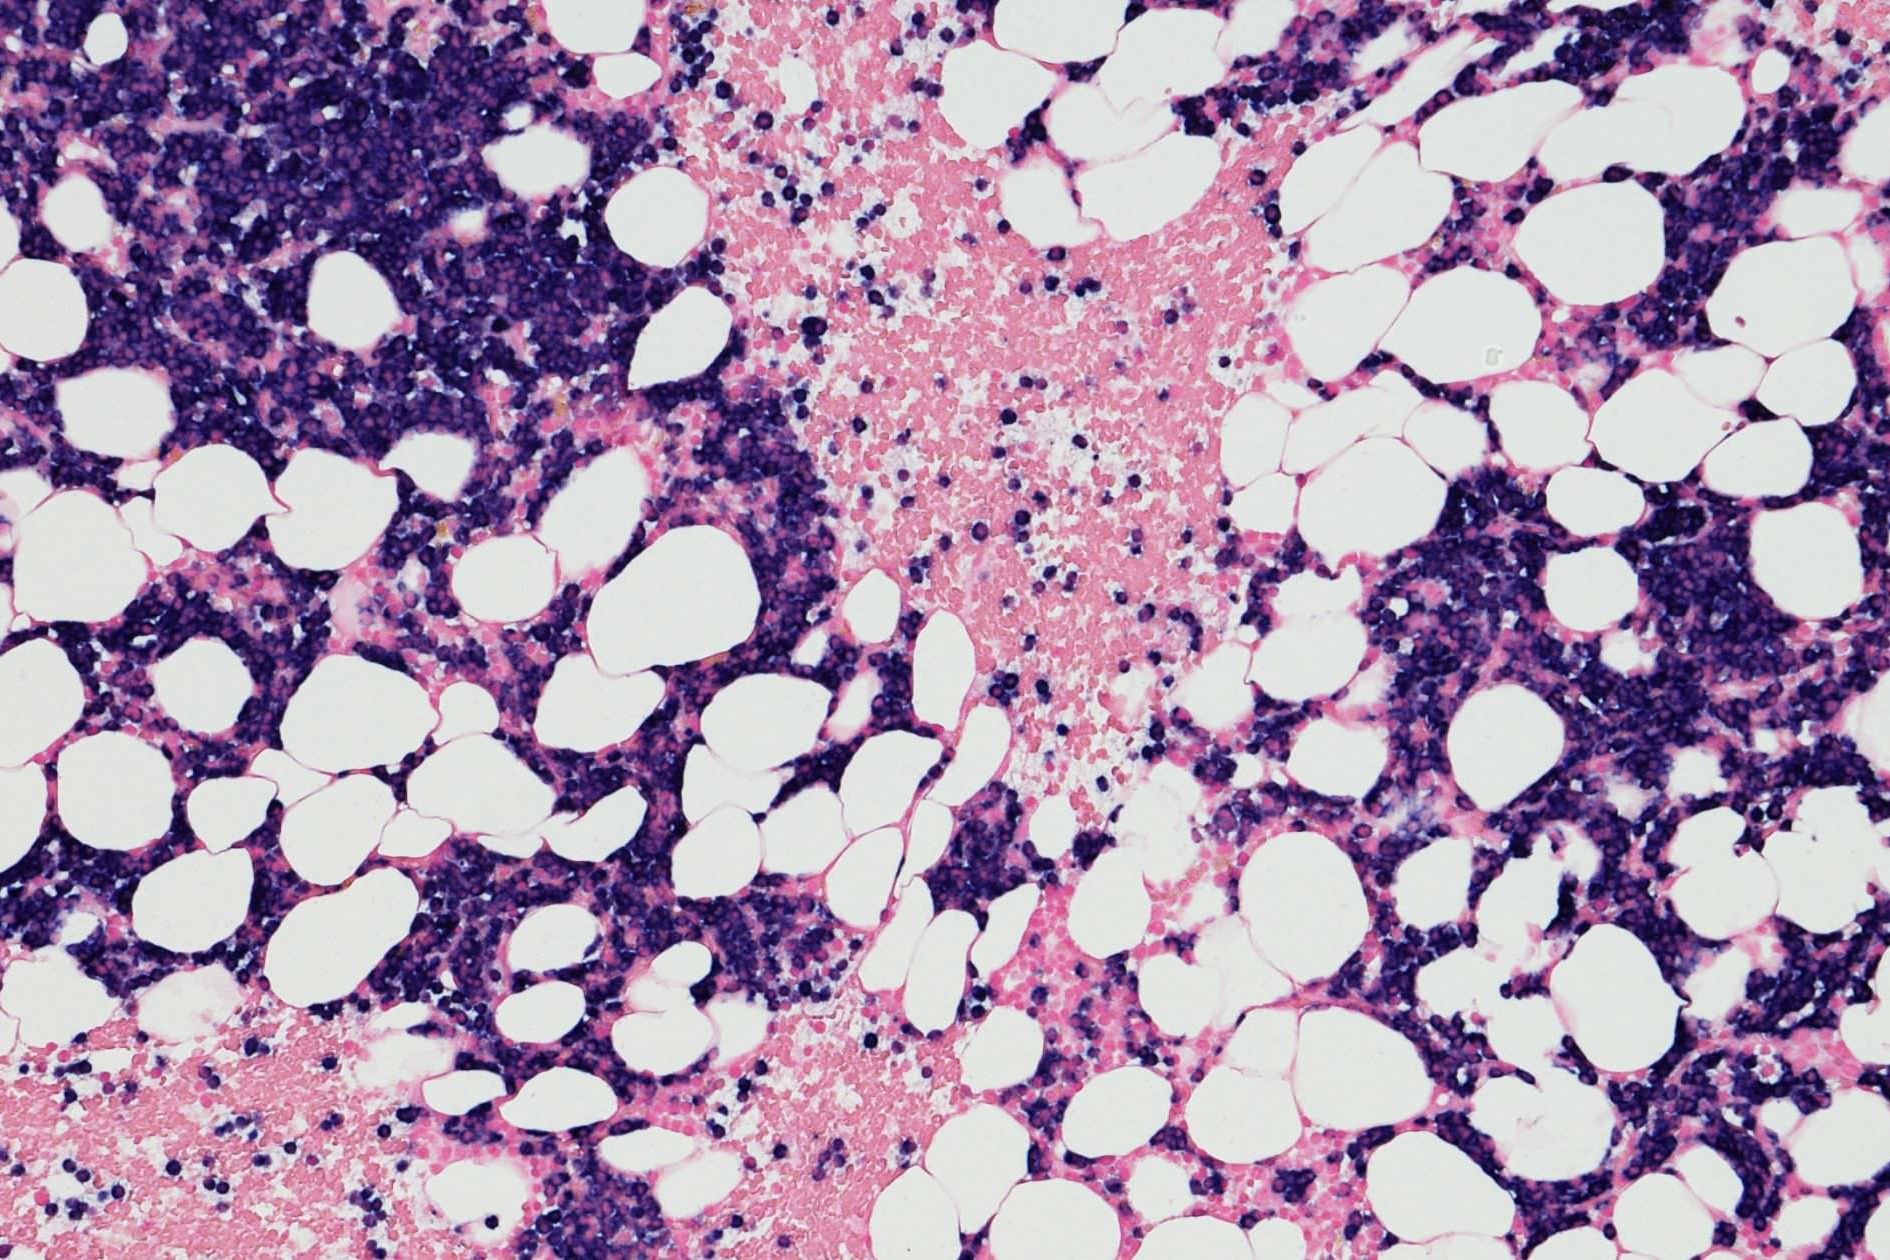

Neutropaenia – An SA Perspective